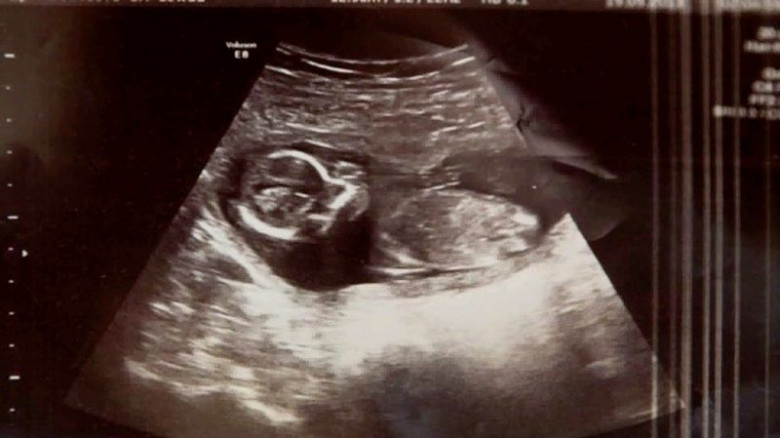

Несчастной женщине дали таблетки для медикаментозного аборта. Однако дополнительное обследование показало, что в матке всё еще находятся сгустки крови, для удаления которых необходимо хирургическое вмешательство. Каким же было удивление медиков, когда на финальном осмотре перед операцией они услышали стук сердца ребенка! Мишель по-прежнему была беременна!

В результате Мишель родила крепкую и здоровую девочку, которую назвали Меган. Семья Хьюи была возмущена непрофессионализмом врачей, которые «просмотрели» второго ребенка и поставили его жизнь под угрозу. Но радость от чудесного рождения дочери затмила все негативные эмоции. Поэтому Мишель и Росс решили не омрачать себе жизнь судебными тяжбами, а сконцентрировались на воспитании малютки Меган, а также ее сестричке Ма и братике Ное. А случившееся с ними воспринимают не иначе как чудо!